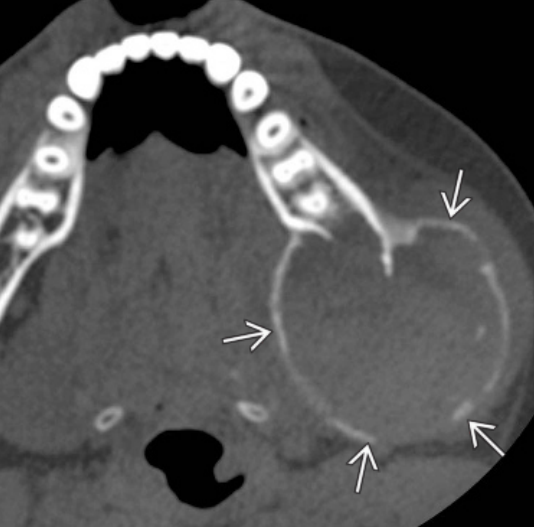

Οι κύστεις αυτές είναι ψευδοκύστεις γιατί εμφανίζονται ακτινογραφικά σαν κυστικές βλάβες, μικροσκοπικά όμως δεν έχουν επιθηλιακή επένδυση. Η ανευρυσματική οστική κύστη αντιπροσωπεύει μια καλοήθη οστική βλάβη, η οποία μπορεί να παρουσιαστεί στην άνω ή την κάτω γνάθο, καθώς και σε άλλα οστά. Πιο συγκεκριμένα, εντός του κρανιοπροσωπικού συμπλέγματος, περίπου το 40% των βλαβών αυτών εμφανίζεται στην κάτω γνάθο και το 25% στην άνω.

Οι ανευρυσματικές οστικές κύστεις εμφανίζονται τυπικά σε ασθενείς νεότερους των 30 ετών.

Όταν εμπλέκονται η άνω και η κάτω γνάθος, επηρεάζονται συχνότερα οι πλέον οπίσθιες περιοχές. Πόνος αναφέρεται στο ήμισυ περίπου των ασθενών, ενώ μια σκληρή, άσφυγμη διόγκωση αποτελεί κοινό κλινικό σημείο. Κατά την ακρόαση δεν ακούγεται ροή αίματος, ενδεικτικό ότι το αίμα δεν εντοπίζεται εντός ενός αρτηριακού χώρου. Σε έντονη ψηλάφιση μπορεί να παρουσιαστεί κλυδασμός.

Στην περίπτωση που η κύστη επεκτείνεται και στο φατνιακό τμήμα της άνω και της κάτω γνάθου, τα δόντια είναι δυνατόν να παρεκτοπιστούν με ή χωρίς εξωτερική απορρόφηση των ριζών.